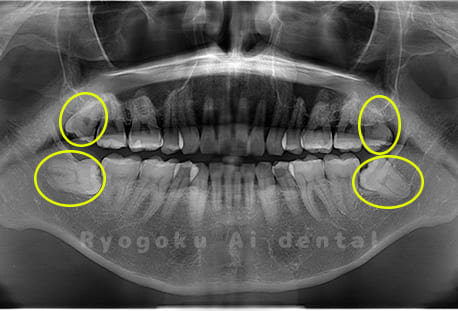

Case03

- 上顎、下顎の親知らず

- 治療内容

- 上下4本の親知らずを抜歯したケースです。

<リスク・副作用>

手術後は痛み、腫れ、痺れなどの副作用が生じる場合があります。